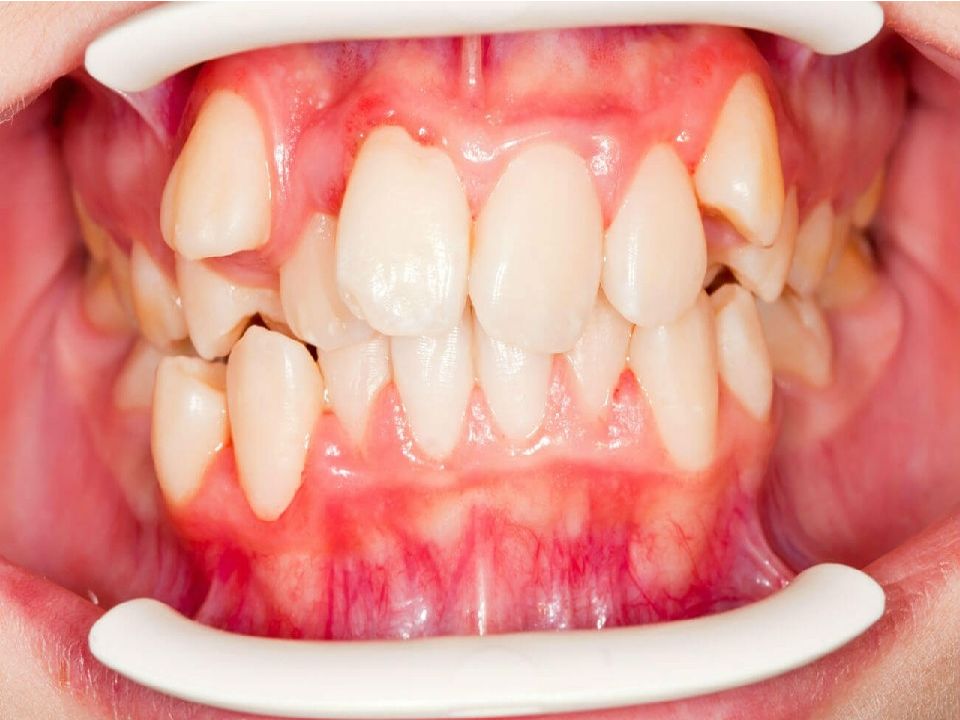

• Клиническая картина полуретенции и дистопии (вестибулярное положение) зуба 4.8